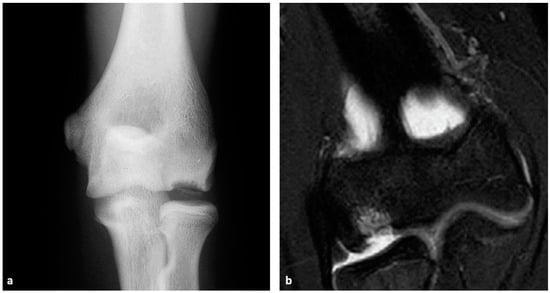

5. Imaging

- Iwasaki, N.; Kamishima, T.; Kato, H.; Funakoshi, T.; Minami, A. A Retrospective Evaluation of Magnetic Resonance Imaging Effectiveness on Capitellar Osteochondritis Dissecans Among Overhead Athletes. Am. J. Sports Med. 2012, 40, 624–630. [Google Scholar] [CrossRef] [PubMed]

- Pu, A.; Jauregui, J.J.; Salmons, H.I.; Weir, T.B.; Abzug, J.M.; Gilotra, M.N. Radiographic Evaluation of Osteochondritis Dissecans of the Humeral Capitellum: A Systematic Review. J. Orthop. 2021, 27, 114–121. [Google Scholar] [CrossRef] [PubMed]

- Nguyen, J.C.; Degnan, A.J.; Barrera, C.A.; Hee, T.P.; Ganley, T.J.; Kijowski, R. Osteochondritis Dissecans of the Elbow in Children: MRI Findings of Instability. AJR Am. J. Roentgenol. 2019, 213, 1145–1151. [Google Scholar] [CrossRef] [PubMed]